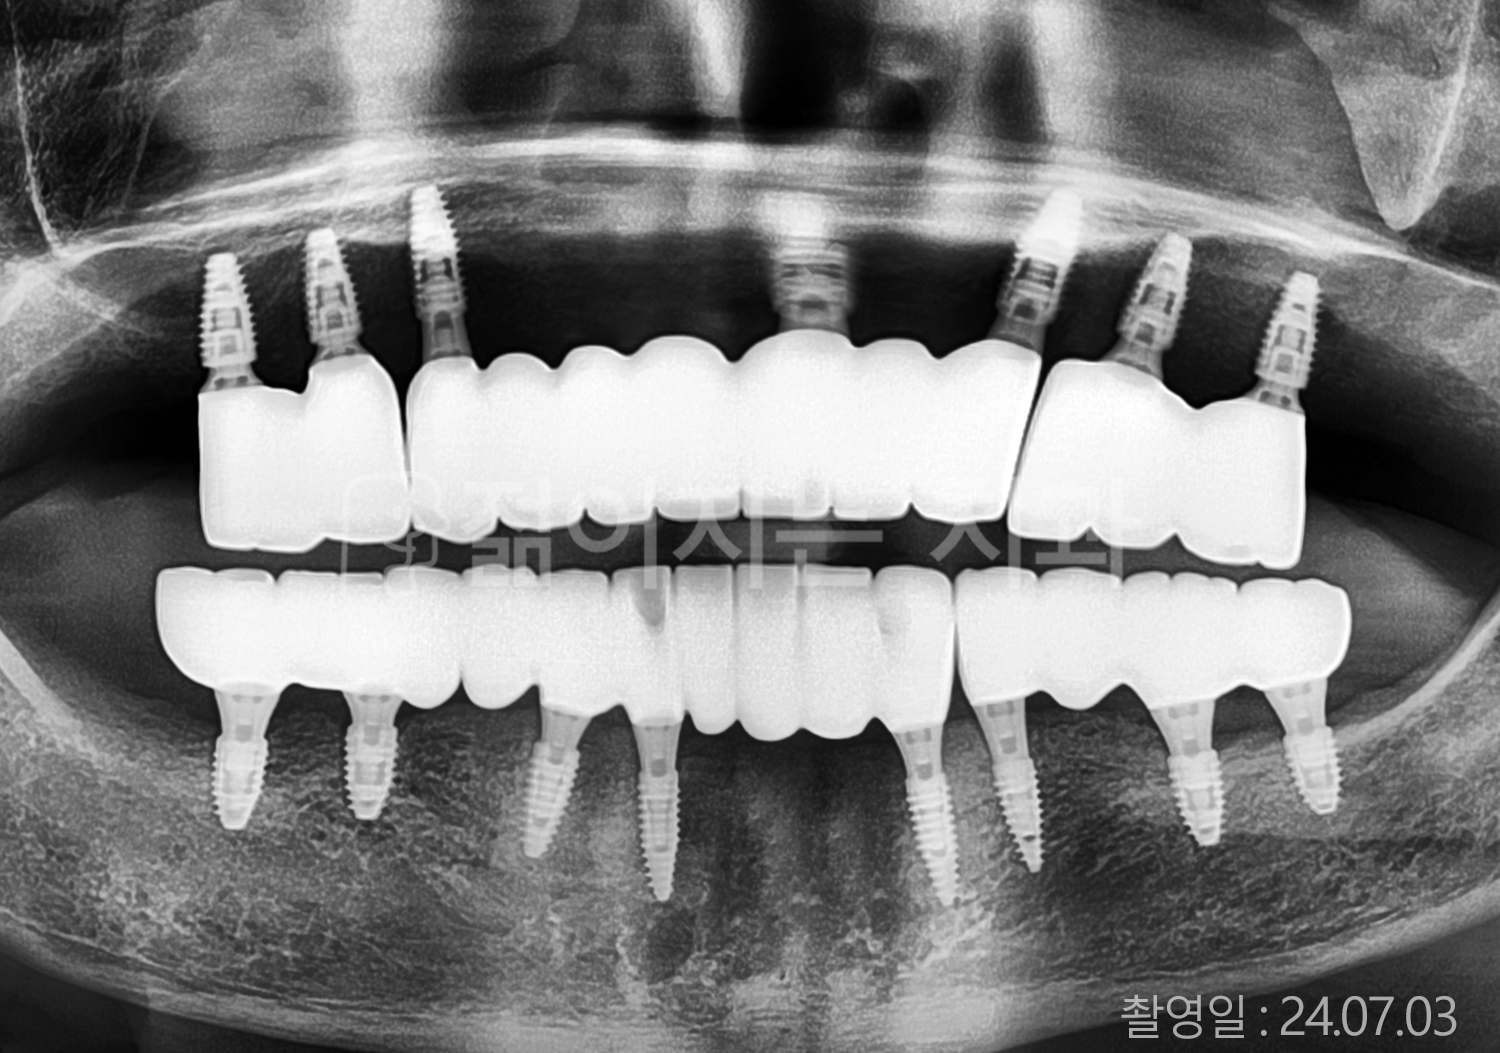

• 70대 고혈압, 고지혈증 전체치아 10개 이상 임플란트

• 60대 당뇨, 간염 전체치아 10개 이상 임플란트

• 80대 골다골증 전체치아 6개 이상 임플란트

• 70대 고혈압, 당뇨 전체치아 10개 이상 임플란트

• 60대 간 질환 전체치아 10개 이상 임플란트

• 60대 전체치아 10개 이상 임플란트

• 70대 전체치아 10개 이상 임플란트

• 50대 전체치아 10개 이상 임플란트

• 60대 고혈압, 고지혈증 전체치아 10개 이상 임플란트

• 40대 고지혈증, 뇌혈관 질환 전체치아 10개 이상 임플란트